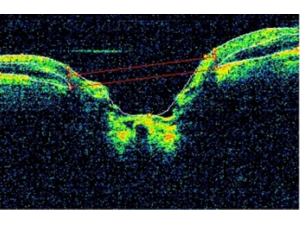

OCT in Glaucoma

By Don Hood, Gus de Moraes, Harsha Rao